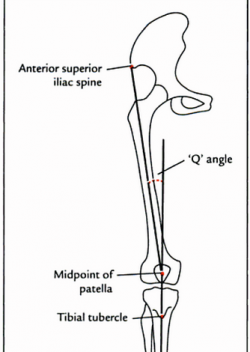

– góc Q:

ở nữ, góc Q phải nhỏ hơn 22 độ với gối duỗi và <9 độ với gối gập 90 độ

ở nam, góc Q phải nhỏ hơn 18 độ với gối duỗi và <8 độ với gối gập 90 độ

Hình: Đo góc Q, góc giữa đường từ gai chậu trước trên (ASIS) đến điểm giữa xương bánh chè và đường từ điểm giữa xương bánh chè đến lồi củ xương chày.

– độ vẹo ngoài của gối với thước đo góc,

– khoảng cách hai mắt cá khi gối chạm nhau (khoảng cách này cần <7,5- 8 cm)